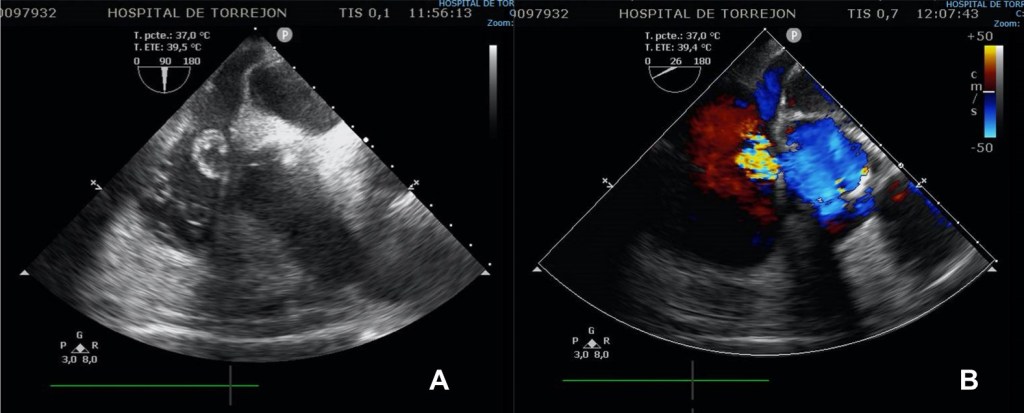

El caso publicado hace referencia a un varón de 68 años, portador de una valvulopatía aórtica moderada en seguimiento y antecedentes de una neurocirugía reciente para resección de una malformación arteriovenosa cerebral, que ingresó en la UCI de nuestro hospital con el diagnóstico de endocarditis infecciosa de la válvula aórtica por Staphilococcus aureus meticilin-resistente. El paciente estaba en situación de parada cardiorespiratoria en el contexto de un bloqueo aurículo-ventricular completo, lo que obligó a la implantación de un marcapasos transitorio. Posteriormente sufrió una crisis tónico-clónica, que obligó a su intubación oro-traqueal. El ecocardiograma demostró la existencia de una insuficiencia aórtica masiva, por lo que se sometió a un reemplazo valvular aórtico emergente. La evolución postoperatoria fue buena, pero una semana después, en un eco de control, se detectó una masa en la aurícula derecha asociada a una comunicación tipo Gerbode directo o supravalvular. Inicialmente se decidió manejo conservador, pero a los 15 días del diagnóstico, coincidiendo con un claro empeoramiento clínico, se objetivó importante aumento del cortocircuito intracardiaco, por lo que el paciente se sometió a una nueva cirugía para corrección quirúrgica del defecto mediante cierre del orificio de salida en la aurícula derecha. El eco de control post-cirugía mostró una prótesis aórtica normofuncionante, ausencia de shunt residual y una válvula tricúspide competente. La evolución posterior discurrió sin incidencias y el paciente fue dado de alta al finalizar el tratamiento antibiótico.